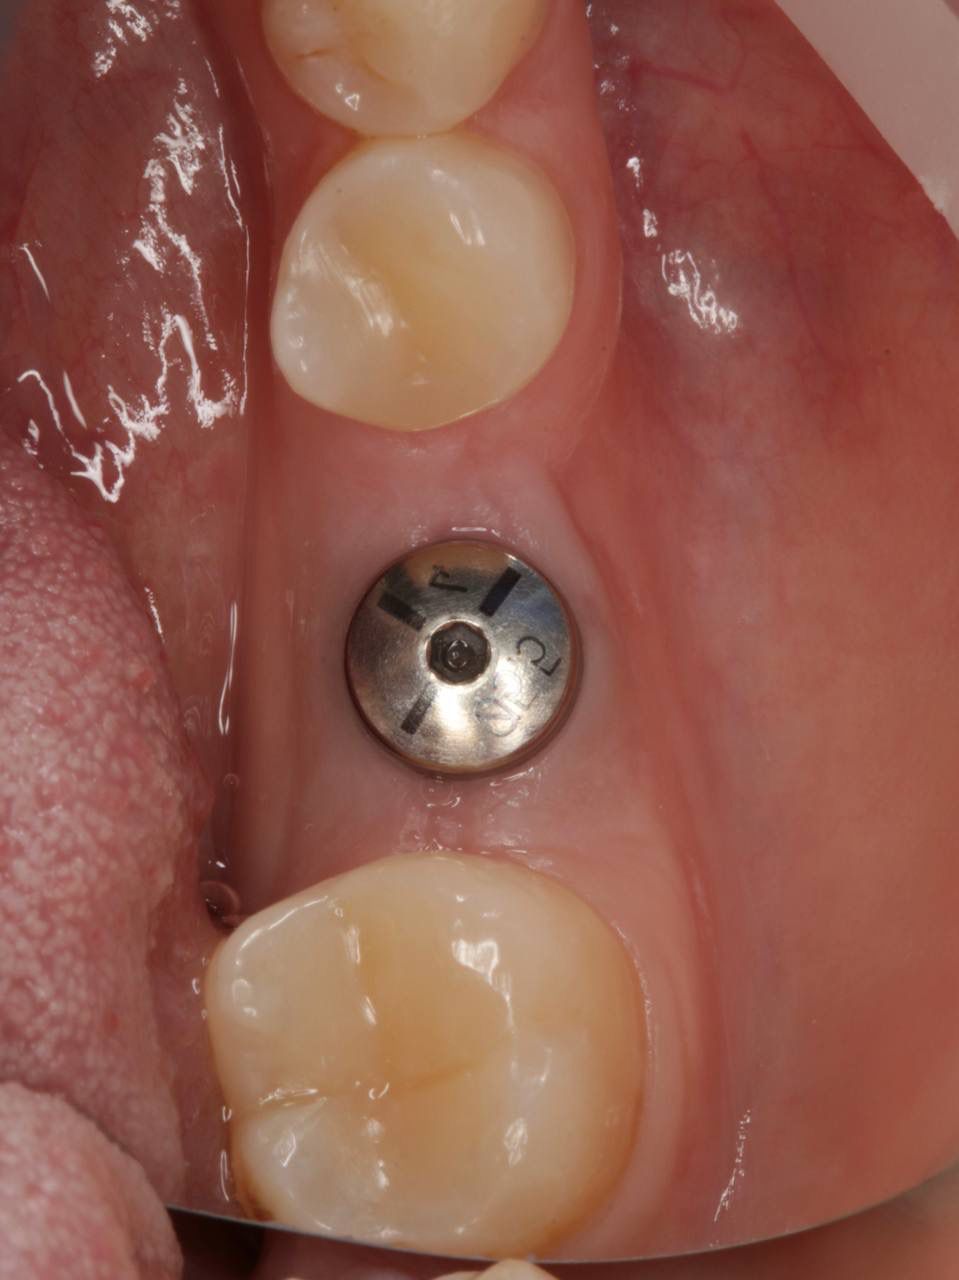

Одномоментная имплантация системой Osstem(Ю. Корея), подшит трансплантат с бугра(для увеличения объема мягких тканей), установлен формирователь десны. Через 3 месяца установлена коронка из диоксида циркония на винтовой фиксации